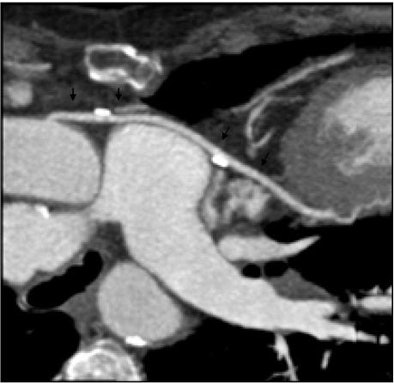

![]() |

| Nongated ultrafast dual-source CT angiography (pitch 3) revealed sharp delineation of coronary artery bypass graft (CABG) at DLP of 134 mGy/cm, despite a high heart rate of 96 beats per minute. |